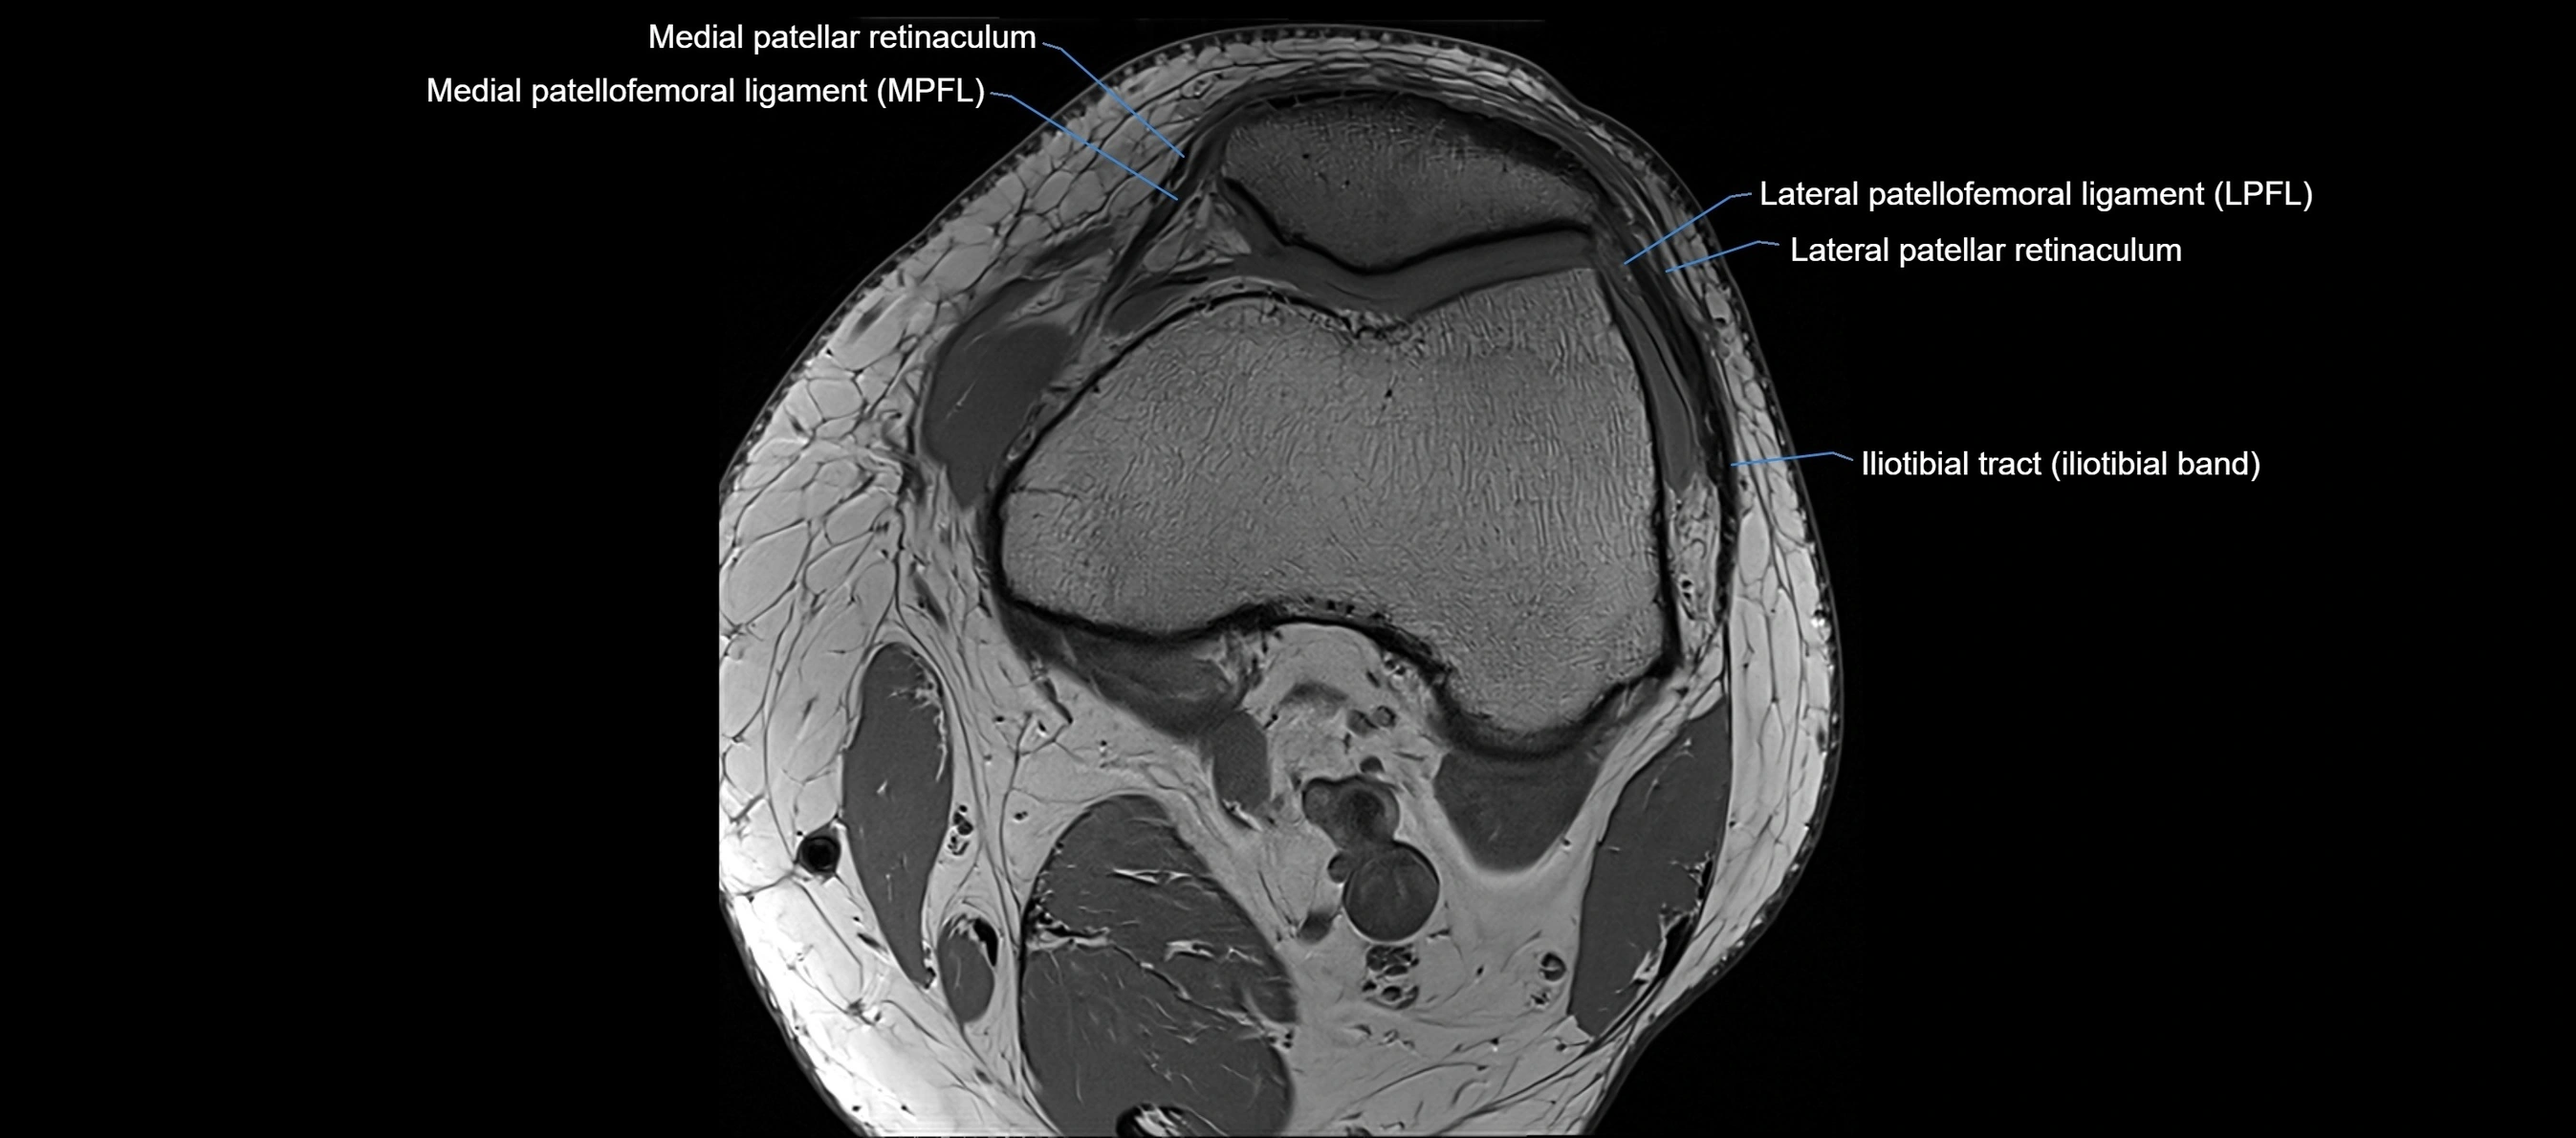

MRI images

image

MRI Appearance

T1-weighted images:

• Normal ACL appears as a low-signal band-like structure crossing the intercondylar notch

• Surrounded by intermediate signal synovial fluid and fat planes

T2-weighted images:

• Normal ACL remains low signal

• Partial or complete tears appear as discontinuity, increased signal, or fiber laxity